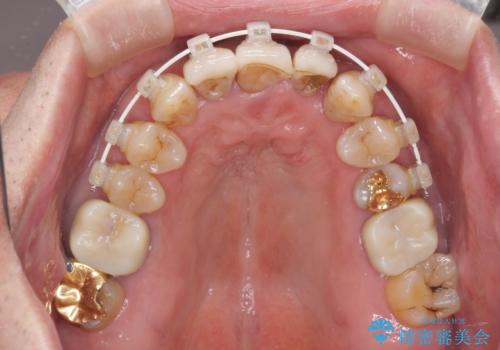

矯正治療と歯周外科処置を併用した審美歯科治療

また、前歯の部分矯正も希望されたため、歯周外科処置と平行して矯正治療を行うこととしました。

患者様ご自身が痛みには強いとおっしゃっていたので、治療中は特に辛いと感じることはなく進めることができました。

気になっていた歯の痛みや歯肉からの出血がなくなり、改善したいと思っていた外見も綺麗に仕上がり、大変満足していただきました。